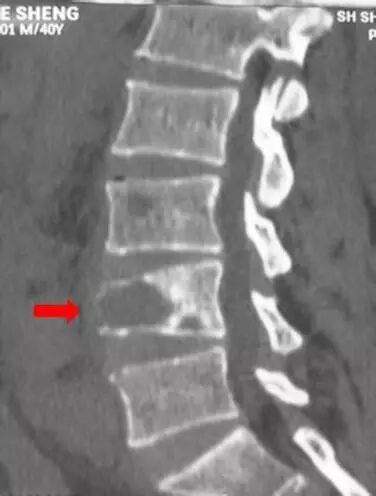

然而,2个月后老张突然出现腰部剧烈疼痛不能活动,紧急送往医院后,行腰椎CT检查重建显示腰4椎体出现了压缩性骨折(箭头所示),疼痛便是由此所致,重建图片上对比可见此时椎体的高度只有原来高度的四分之一了,令人遗憾的是,此时椎体已经无法恢复到正常的高度了。